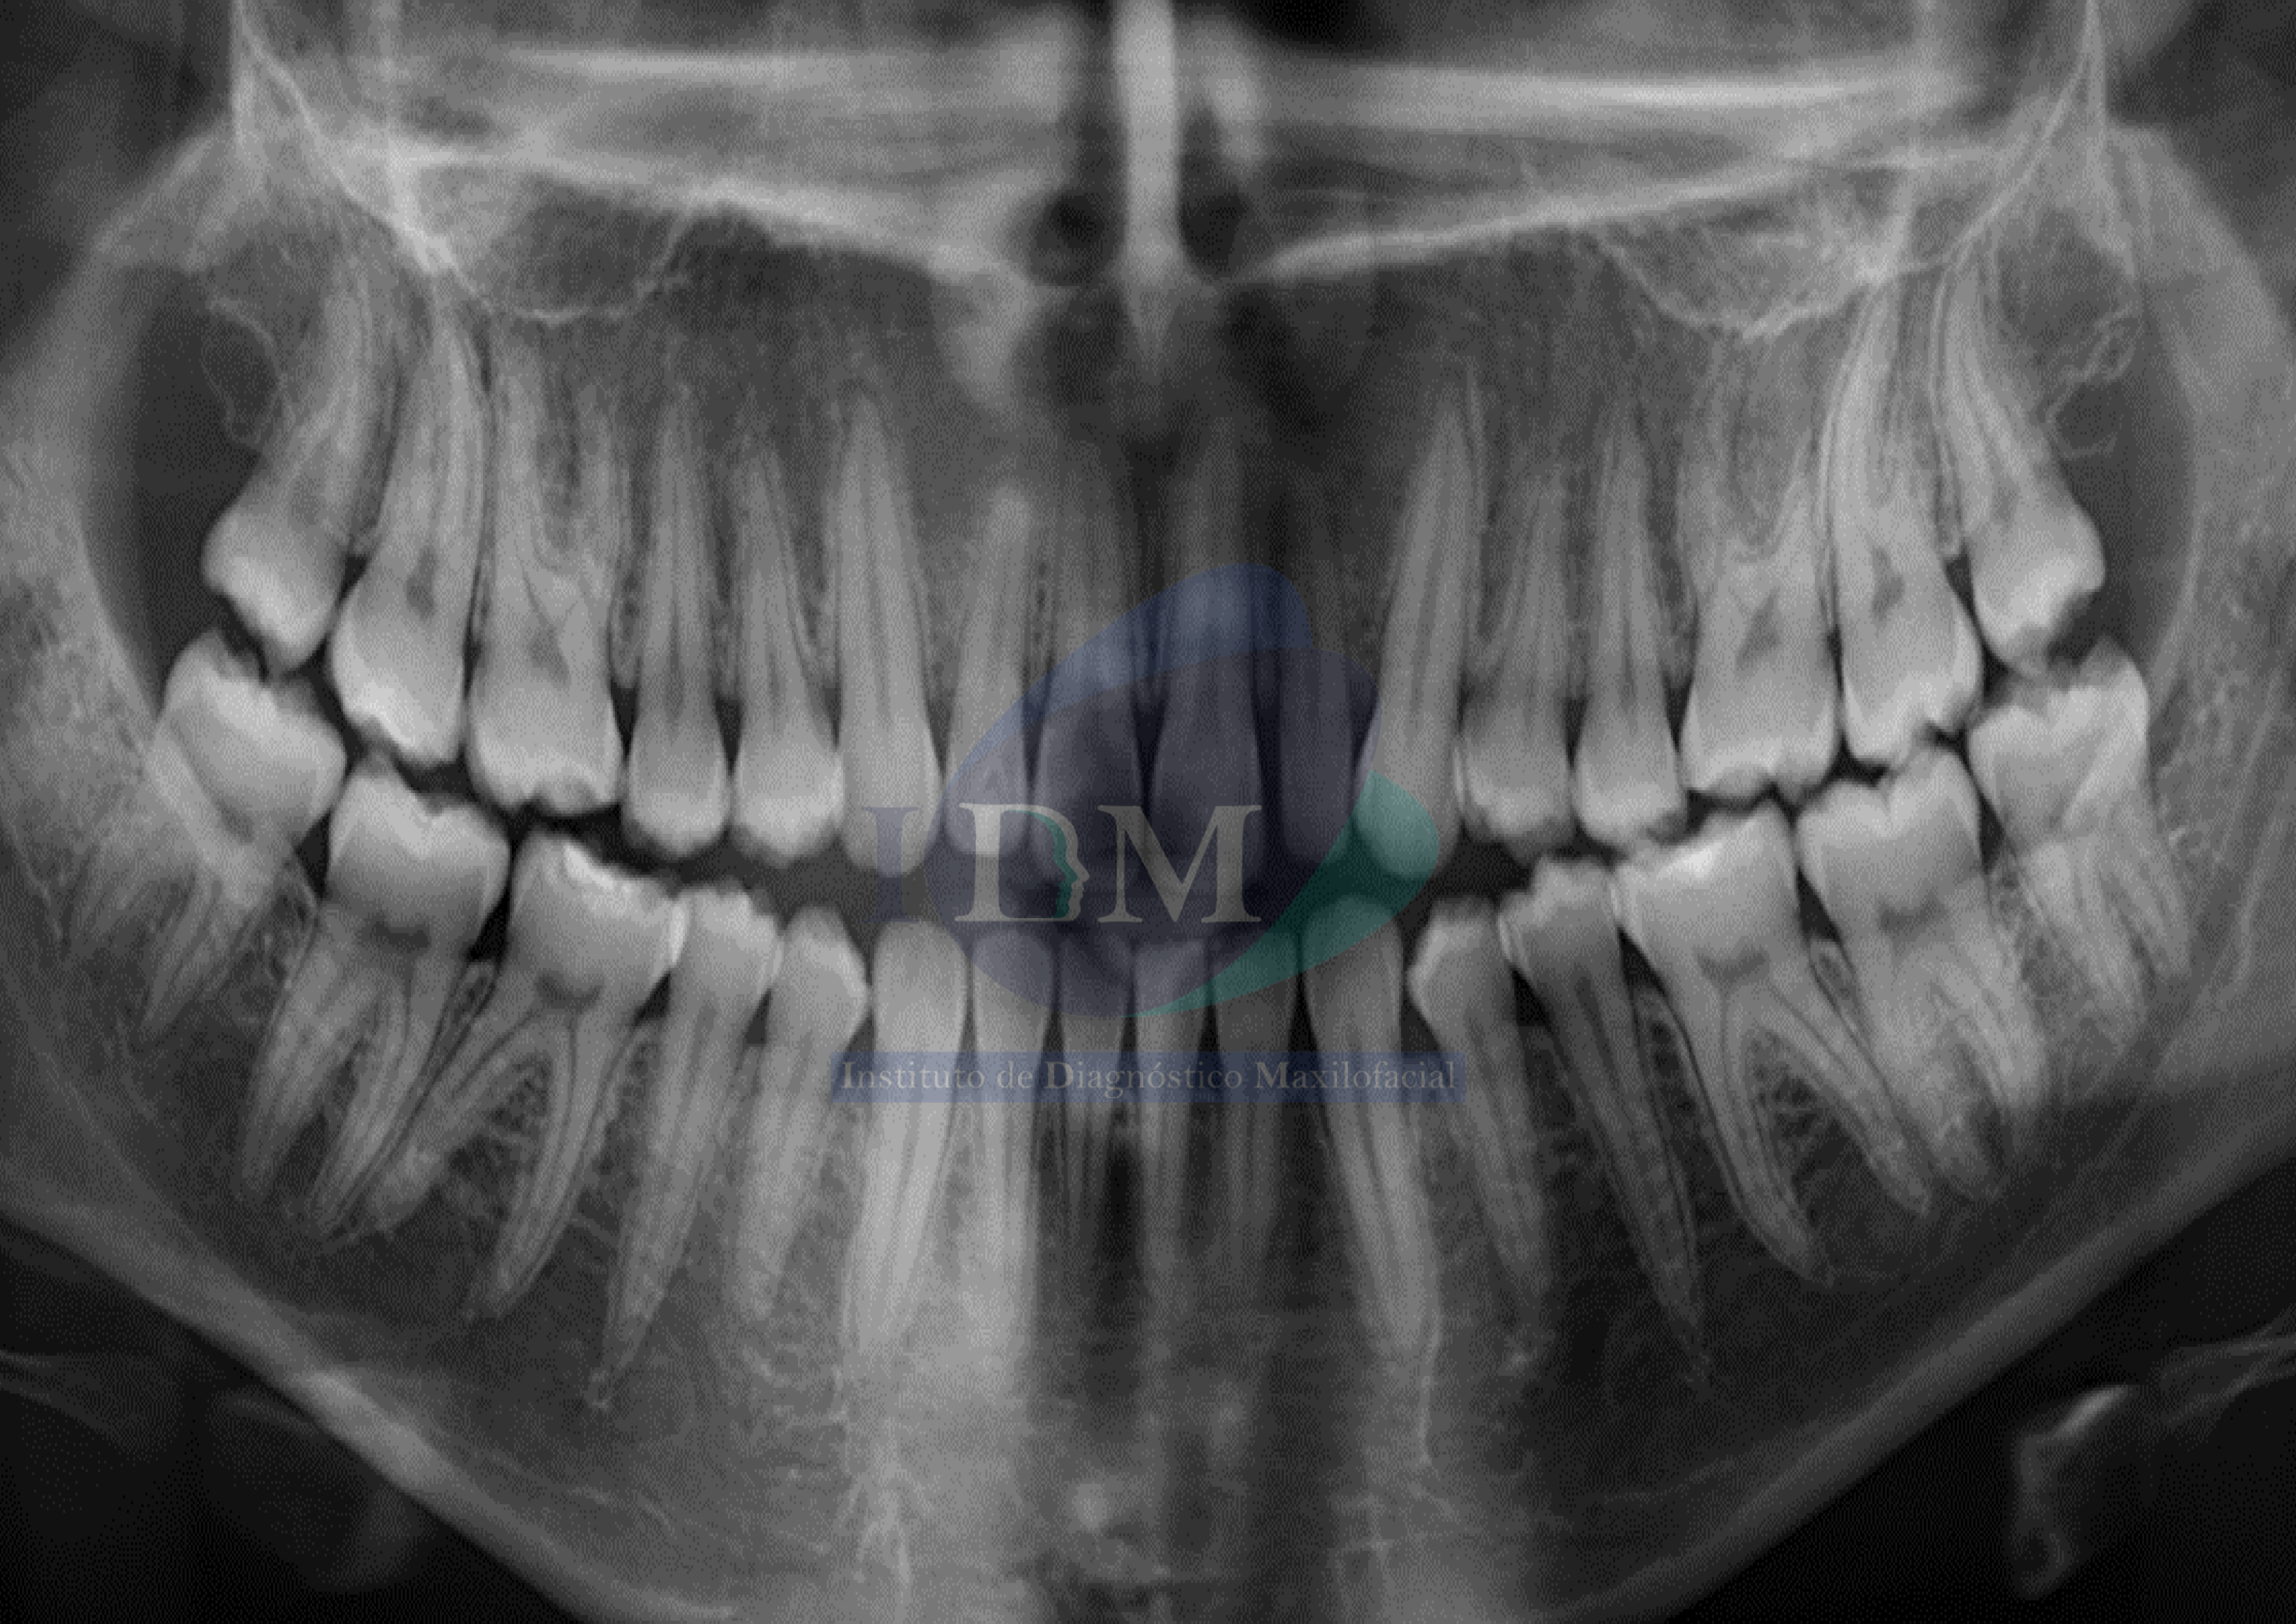

Radiografia Panorámica

A la evaluación de la radiografía panorámica se evidencia diastemas en sector dentario anterior con leve disminución generalizada de la longitud radicular.